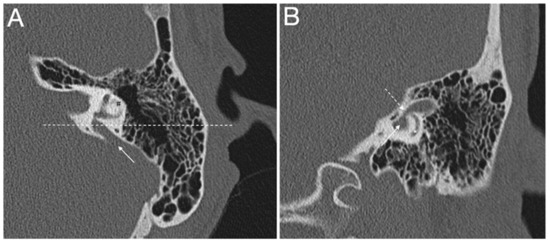

- Lyu, H.; Hong, J.; Yin, D.; Chen, K.; Li, J.; Yang, L.; Zhang, T.; Dai, P. Position of the internal aperture of vestibular aqueduct in patients with enlarged vestibular aqueduct. Otol. Neurotol. 2017, 38, 1198–1204. [Google Scholar] [CrossRef] [PubMed]

- Juliano, A.F.; Ting, E.Y.; Mingkwansook, V.; Hamberg, L.M.; Curtin, H.D. Vestibular aqueduct measurements in the 45 degrees oblique (Poschl) plane. AJNR Am. J. Neuroradiol. 2016, 37, 1331–1337. [Google Scholar] [CrossRef]